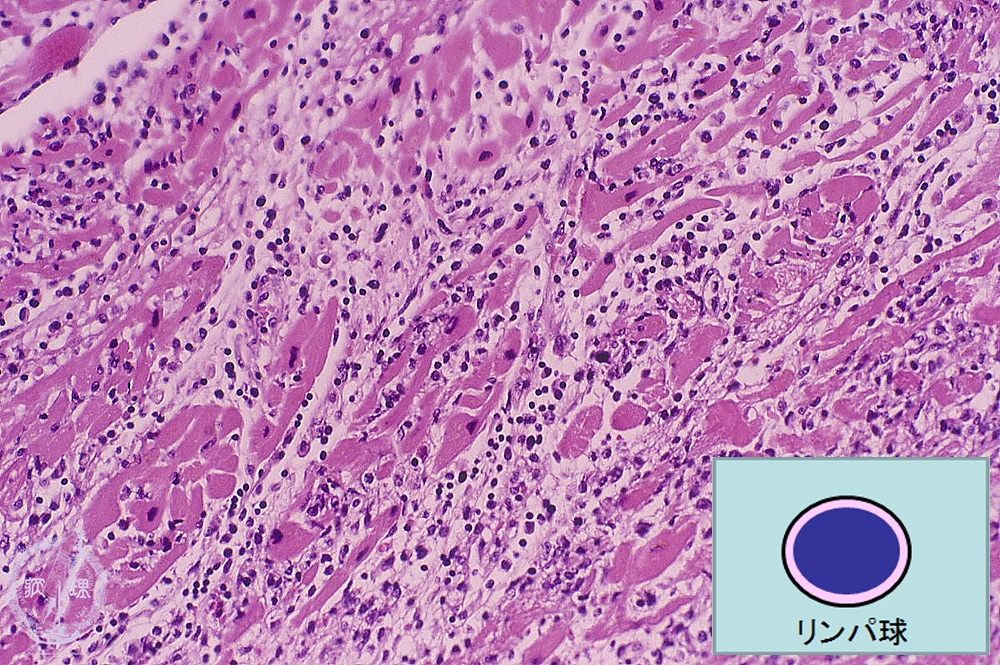

Microscopic image (HE, low power view): There is a marked inflammatory cell infiltrate consisting mainly of lymphocytes. Islands of entrapped myocardium show prominent necrotic change.